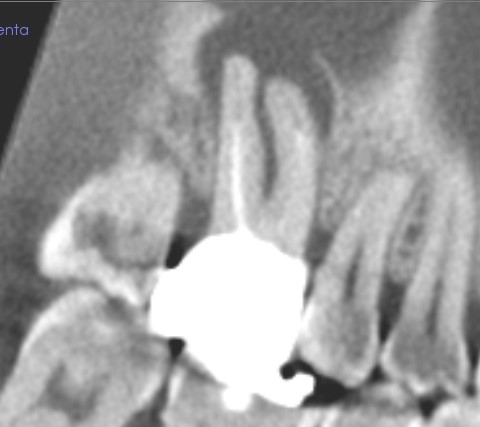

治癒傾向にある、穿孔による歯周組織の骨吸収

半年後のレントゲン写真です。

黒く映る骨が溶けた部分が小さくなり、治癒傾向にあるのが分かります。

今は、噛んでも、普通のときも、不調は感じないそうです。